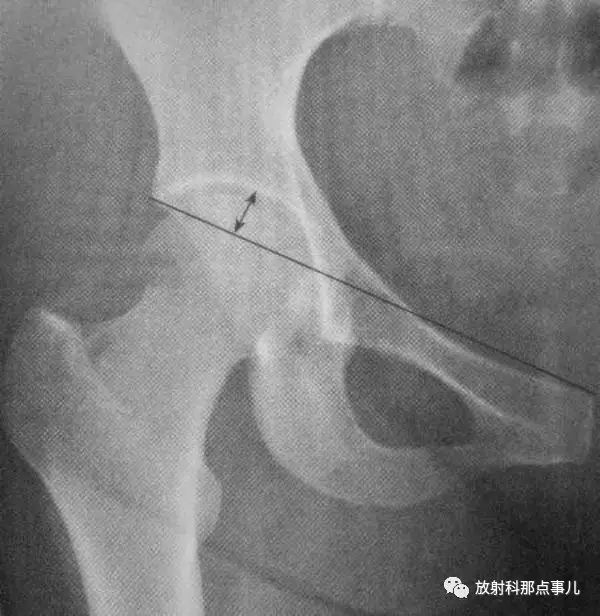

Power角

在骨盆正位片上,通过两侧髂前上棘作一水平线,然后再划股骨颈骨折线的延长线,两线相交所成的夹角。此角小于30° 者,为外展型骨折,骨折易愈合;大于30° ~90° 者,为内收型骨折,需手术纠正。

Linton角

在髋关节正位片上,先划股骨干纵轴线垂线,再划股骨颈骨折线的延长线,两线相交所成的夹角。此角小于30° 者,为外展型骨折,骨折易愈合;大于30° ~90° 者,为内收型骨折,需手术纠正。